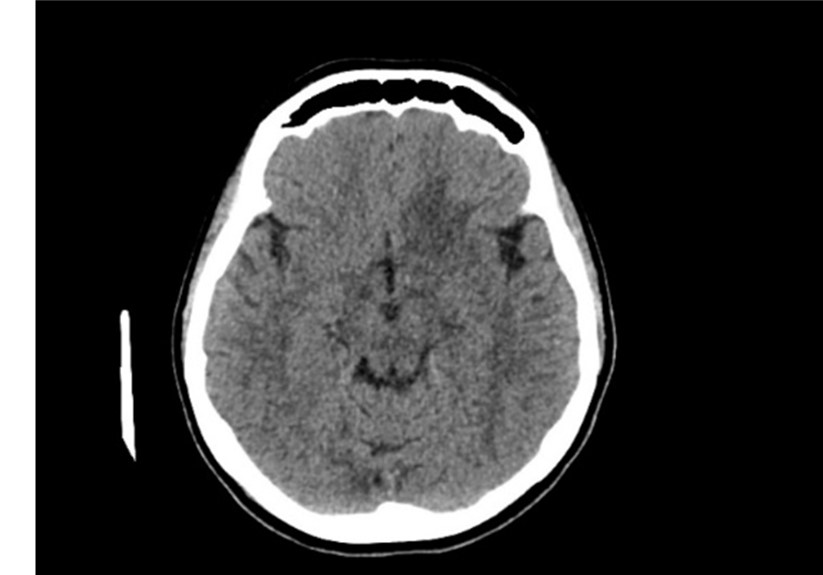

She initiated with NCCT (non-contrast enhanced CT) that showed hypo-dense poorly defined lesion at the base of left frontal lobe, she continued with CECT (contrast-enhanced CT) that showed no defined enhancement (Figure 2, 3).

Figure 2: Axial NNCT (non-contrast enhanced CT) shows poorly defined hypodense lesion at the base of LT frontal lobe.

Figure 3: Axial CECT (contrast enhanced CT) shows no specific enhancement of the lesion.